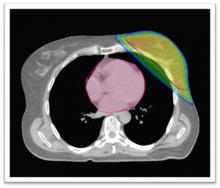

Moderně vedená léčba radioaktivním zářením, tedy i při konkomitantní chemoradioterapii, je v současné době prováděna konformně. Cílem konformní radioterapie (conform = přizpůsobit) je přizpůsobit tvar ozařovaného objemu nepravidelnému objemu nádorového ložiska. Snižuje se riziko vzniku...

Důležitou podmínkou účinné a bezpečné léčby zářením je její precizní naplánování. Indikace léčby zářením u každého pacienta by měla vzejít z rozhodnutí týmu, ve kterém je obvykle radiolog, patolog, chirurg, radiační onkolog a chemoterapeut, popřípadě i jiní odborníci. Dále...